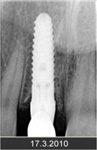

Klasickým příkladem a indikací pro použití implantátu je ztráta jednoho zubu (v tomto případě v předním – frontálním úseku) v jinak zdravém, nepoškozeném chrupu.

Náhrada jednoho zubu pomocí implantátu je možná také v postranním úseku chrupu. Při ztrátě většího počtu zubů ve frontálním nebo postranním úseku může být mezer uzavřena větším počtem jednotlivých implantátů.

Podmínkou je opět dostatečné množství kosti.